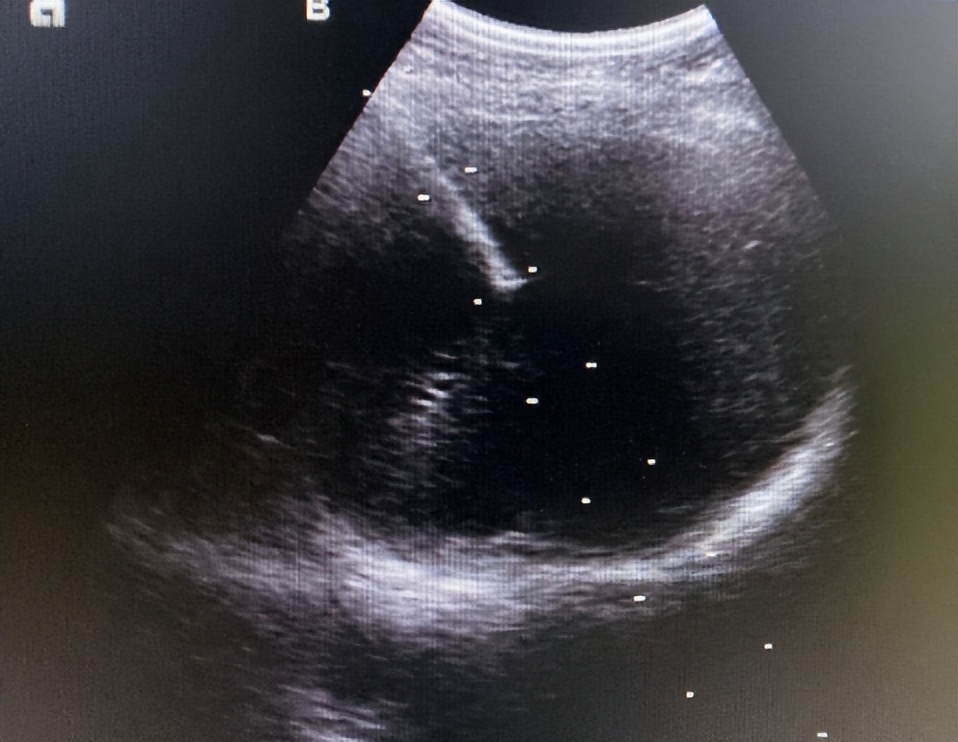

B超引导下肝肿物消融治疗